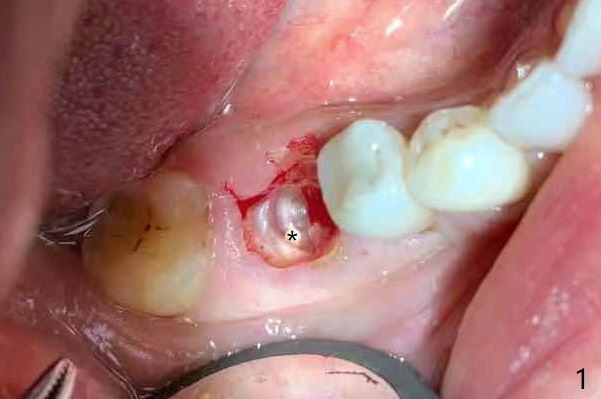

牙冠断裂,好像容易保留牙根,其实还挺多工作。使用12毫米平磨钻头后,中隔中央形成凹陷,不过使用2.2x7.3毫米钻头后,钻洞开始偏移远中(图一)。完成3.5x11.5毫米钻洞,4x10毫米报废植体扭力很高(图二)。为了植入5x11毫米植体(扭力35Ncm),必须使用4.5x11.5毫米钻头(图三)。虽然根尖骨质不多,稳定性部分来自残余颊侧,舌侧中隔。即刻放置的基台远中舌侧必须大量磨去(图四:^)才有足够空间做临时牙冠,说明牙冠会折裂病人咬合力大。保留牙根工作量大,仍有偏差(与图五(设计)相比),仿佛好处不大,以后少做。由于临时牙冠舌侧做的大些,术后八天取出修正,伤口愈合正常(图六)。术后一个月一部分骨粉好像被转化为牙龈(图七)。术后3.5月病人抱怨咀嚼疼痛,植体松动,放置愈合基台。一个月后植体仍松动,疼痛(图八)。术后6.5月,植体不再松动,放置修复基台(图九),取模。